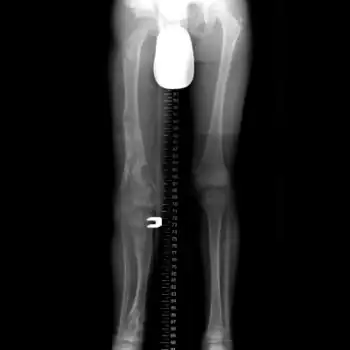

X-ray hips and legs: multiple enchondroma -

X-ray legs: Ollier disease -

Enchondromatosis is the presence of multiple enchondromas, occurring as part of Ollier disease, Maffucci syndrome, or metachondromatosis.[3] It has a tendency to affect short tubular bones of the hands and feet, but can occur in long bones, shoulder blades and hips.[3] It presents with bone deformity, lumps, or broken bone, typically in a child.[2]